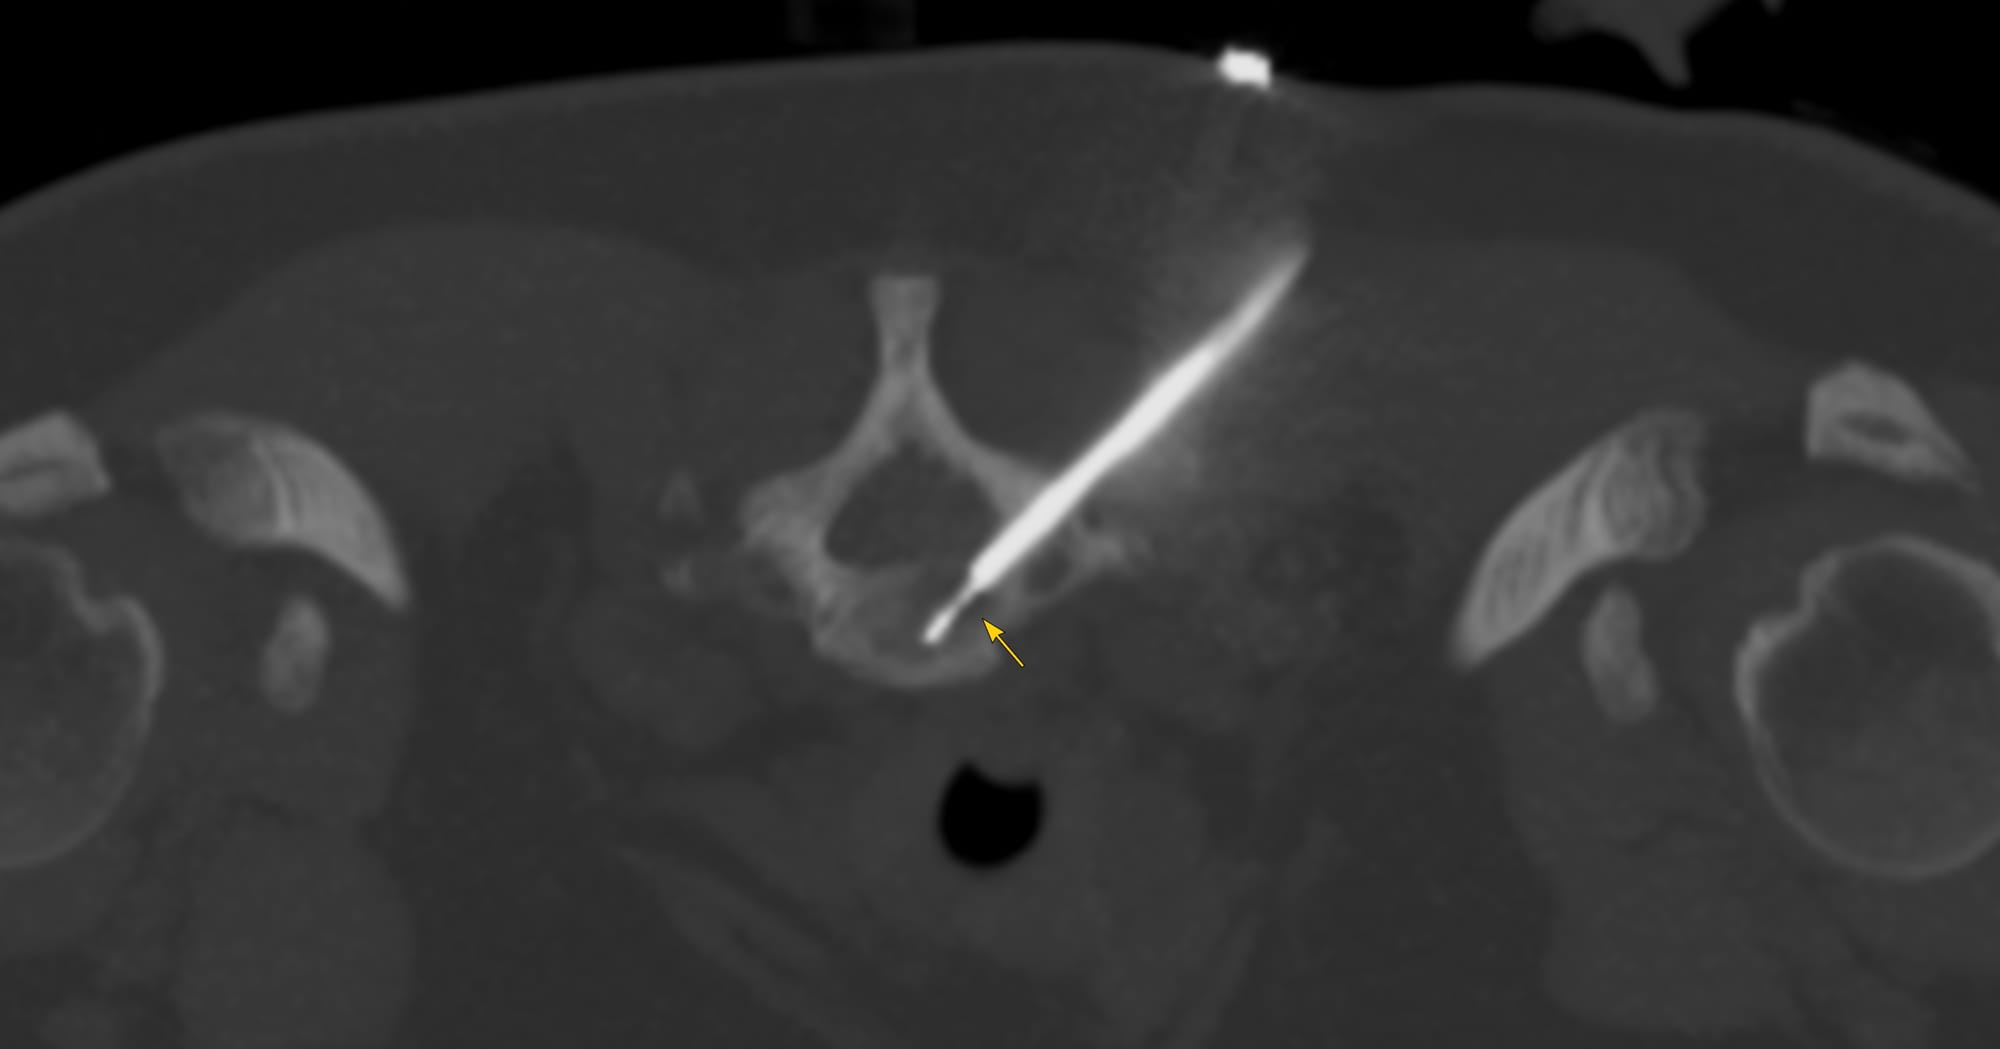

Case 167: Transpedicular Approach for a Lower Cervical Body Lesion